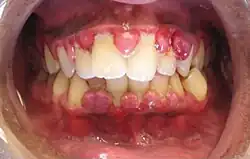

| Gingival enlargement can be a feature in some periodontal diseases. | |